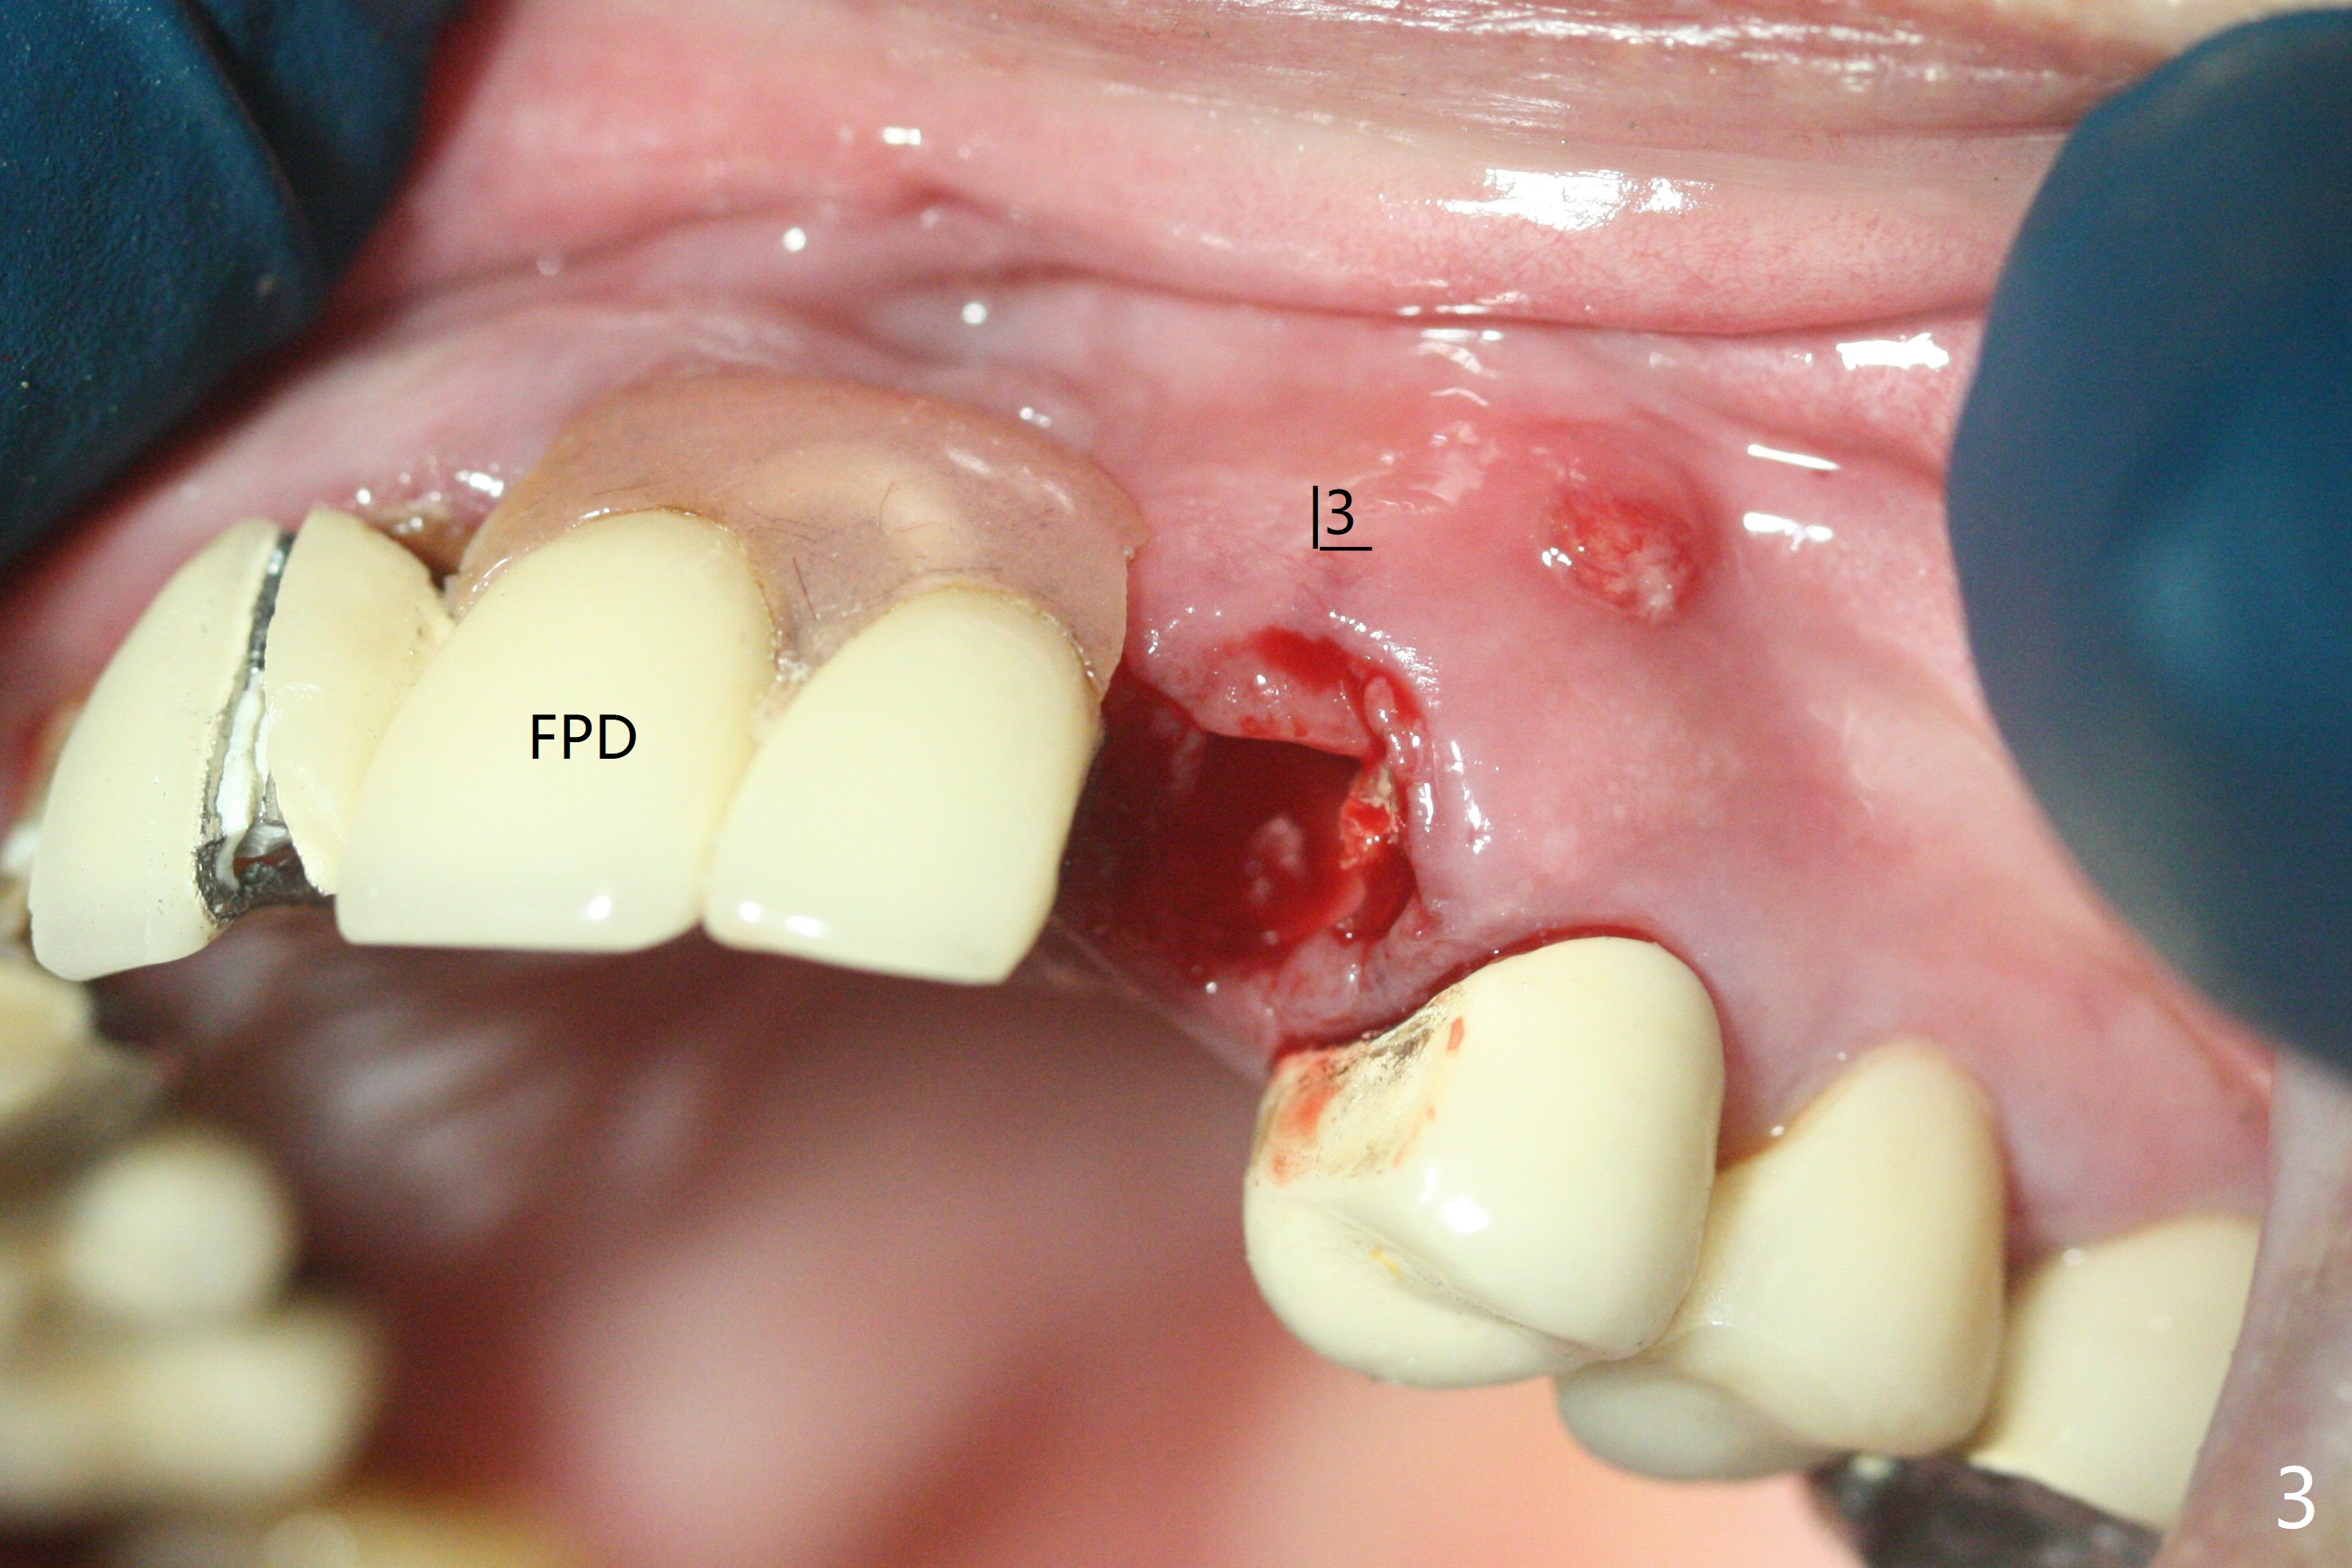

上前牙桥撤除显示右上1,2牙齿以及左上2叶片状植体好像可以保留,而左上3牙齿不能(图一,二(<:托牙边缘压迹)),拔除左上3牙齿后, 暂时把牙桥回位(图三:FPD(已经去除左上3号牙牙冠))作为3号牙种植位置参考(图四至六(G:骨粉))。其实植入前,当最后一个钻头还在原位,将PRF膜和粘性骨放置颊侧根尖(但愿骨粉能放深点),因为那里骨质很薄,好像缺损。由于植体扭力很低(大约5Ncm),放置骨粉覆盖植体(图七),为了不用缝线,涂牙周胶水(图八),放置胶原膜(图九),再涂胶水(图十)固定,最后利用右上1,2号牙(去龋,build-up后)和左上2植体制作临时牙桥,并且覆盖左上3牙槽窝。术后即刻CT显示植体颊侧(B)骨粉(图十一:*)。<:植体根尖仍有间隙,植体应该再长2毫米,初步稳定性会好些。左上3植牙愈合后,将与左上2植体制作左上1-3悬臂桥,右上1,2号牙将做根管治疗,桩,牙冠。临时牙桥术后十一天松动,右上一,二牙牙髓活性测定正常,深洗后,再次build up,不小心把左上3胶原膜吹掉,下面骨粉还稳定。术后三周病人回来做右上六种植,前牙临时修复体(图十二)需要修改(图十三)。拍摄三个方向照片显示前牙牙龈乳头(颊侧和咬合面)。